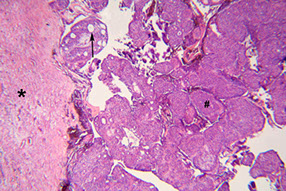

Adenomatoid Odontogenic Tumor (AOT)

- aka adenoameloblastoma

Odontogenic tumor arising from enamel organ or dental lamina

- rare; seen in younger pts, 2F>1M; usually in anterior maxilla, and most are assoc c an impacted canine tooth

Imaging: radiolucency around an unerupted tooth extending past the cementoenamel junction

- usually has faint flecks of radiopacities surrounded by radiolucent zone

Gross: crown of tooth usually projects into cystic cavity

Micro: well-circ, central prolif of duct-like epithelium surrounded by small foci of calcification

- may see rosettes, trabecular or cribriform patterns of epithelium

- columnar-type cells c basal nuclei and clear cytoplasm can looklike pre-ameloblasts

- eosinophilic material seen in bwt tumor cells and in ductlike structures

Tx: enucleation

AOT c fibrous connective tissue capsule (*), nodular aggs of cells (#), and duct-like strucures (->)

Gland-like spaces surrounded by cuboidal to columnar cells (->)

AOT